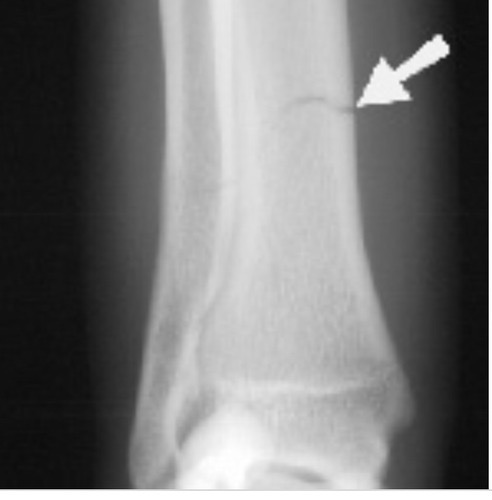

Stress fracture

Due to repetitive use. Also called hairline fracture. Appears like a crack on a x-ray